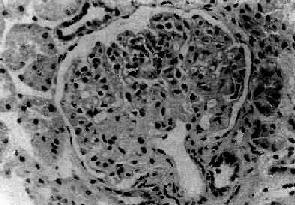

七、局灶性节段性肾小球硬化局灶性节段性肾小球硬化(focal segmental glomeralosclerosis)病变为局灶性,节段性,仅累及少数或部分肾小球。病变的肾小球毛细血管丛呈节段性硬化,是引起肾病综合征常见的原因之一。多见于儿童和青年人。此型肾炎病变为进行性,病人对激素治疗效果不理想。多继续发展为弥漫性硬化性肾小球肾炎。 【病理变化】 病变为局灶性,往往从肾皮质深部近髓质部分的少数肾小球开始。早期仅少数肾小球受累,其他肾小球无明显病变或病变轻微。病变的肾小球毛细血管丛的部分毛细血管萎陷,系膜增宽、硬化、玻璃样变(图12-21)。系膜内和毛细血管内常有脂滴和玻璃样物质沉积。有时可见吞噬脂类的泡沫细胞聚积。电镜下可见硬化部分毛细血管基底膜皱缩,厚薄不均匀。其间可见电子致密物和脂滴沉积。上皮细胞足突消失。免疫荧光检查可见病变肾小球内有免疫球蛋白和补体沉积,主要为IgM和C3。

图12-21 局灶性节段性肾小球硬化 肾小球毛细血管丛的一段硬化,玻璃样变 病变继续发展,受累的肾小球逐渐增多。有些肾小球毛细血管丛可全部纤维化、硬化、玻璃样变(球性硬化)。相应的肾小管也萎缩、纤维化。肾间质纤维组织增生,有少量淋巴细胞和单核细胞浸润,有时并可见泡沫细胞聚积。晚期,大量肾小球硬化可发展为弥漫性硬化性肾小球肾炎而导致肾功能不全。 【临床病理联系和结局】 局灶性节段性肾小球硬化病人约80%表现为肾病综合征。但与一般肾病综合征不同,其中约2/3同时伴有血尿,并常有高血压。大量蛋白尿,多为非选择性。病人对激素治疗效果不好,有效率仅为20%~30%。病变为进行性,常继续发展,可导致肾功能不全。一般儿童预后比成年人好。